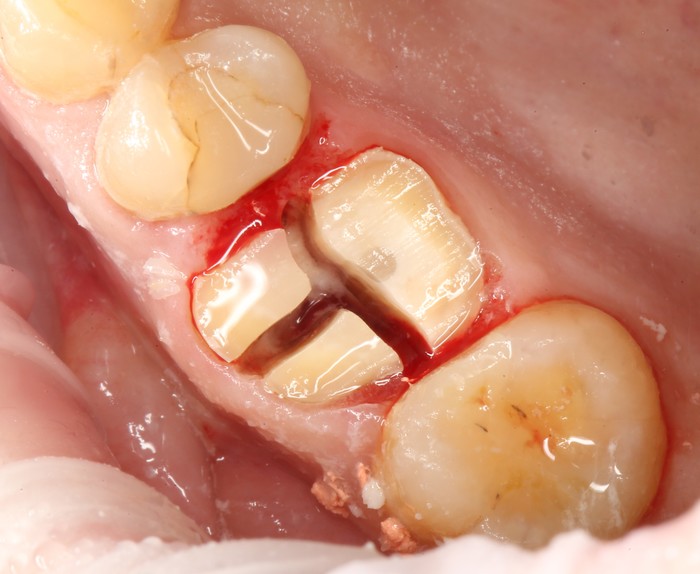

После снятия коронки:

Выкрутили абатмент:

Установлена заглушка, которая закрывает шахту имплантата.

Теперь необходимо выждать около 2-х месяцев для того, чтобы десна восстановилась (Пациентка это время ходила со специальной капой, которая имитирует наличие зуба).

Далее проведена пластика десны, снова два месяца ожиданий и установка временной коронки:

Ну, такое, согласен, но это начало.